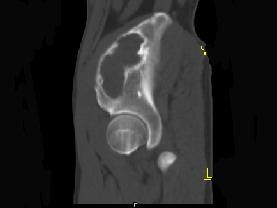

问题 男,34岁,左髂骨疼痛,有皮肤色素沉着,性早熟等,请结合所提供图像,选择最佳答案 ( )

选项 A、内生软骨瘤 B、骨巨细胞瘤 C、畸形性骨炎 D、骨纤维结构不良 E、非骨化性纤维瘤

答案 D